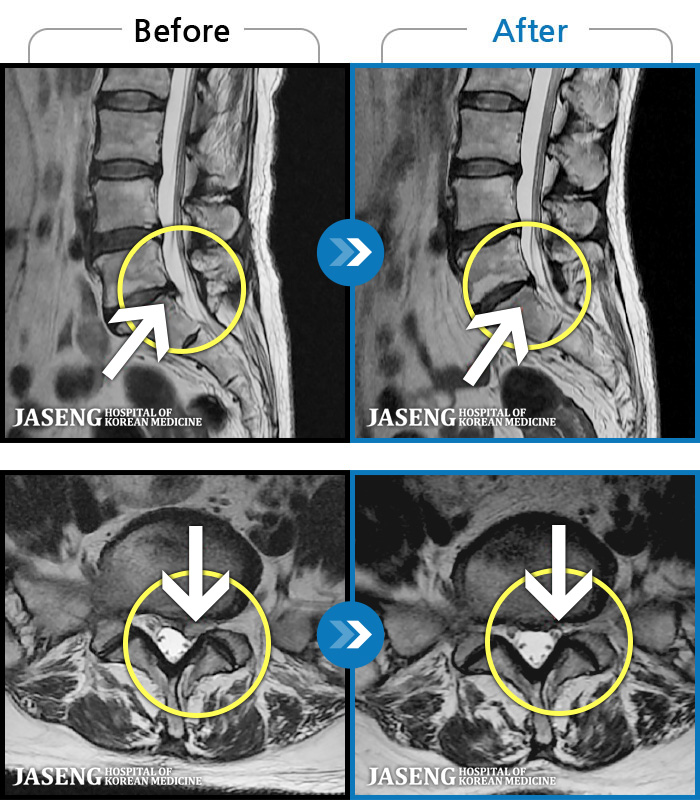

MRI 치료사례

엉덩이의 왼쪽 부위 및 하지방사통이 심각하여 보행이 불가한 상태에서 내원하셨습니다.